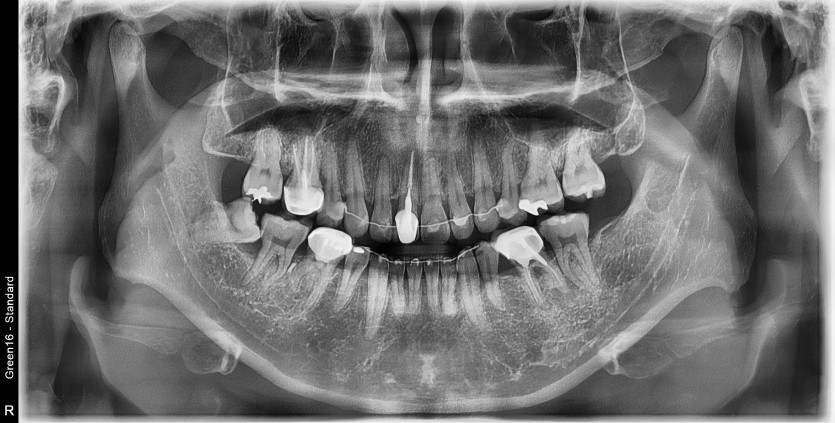

#48 사랑니 발치

구강 외과 전문의가 당일 발치했습니다.